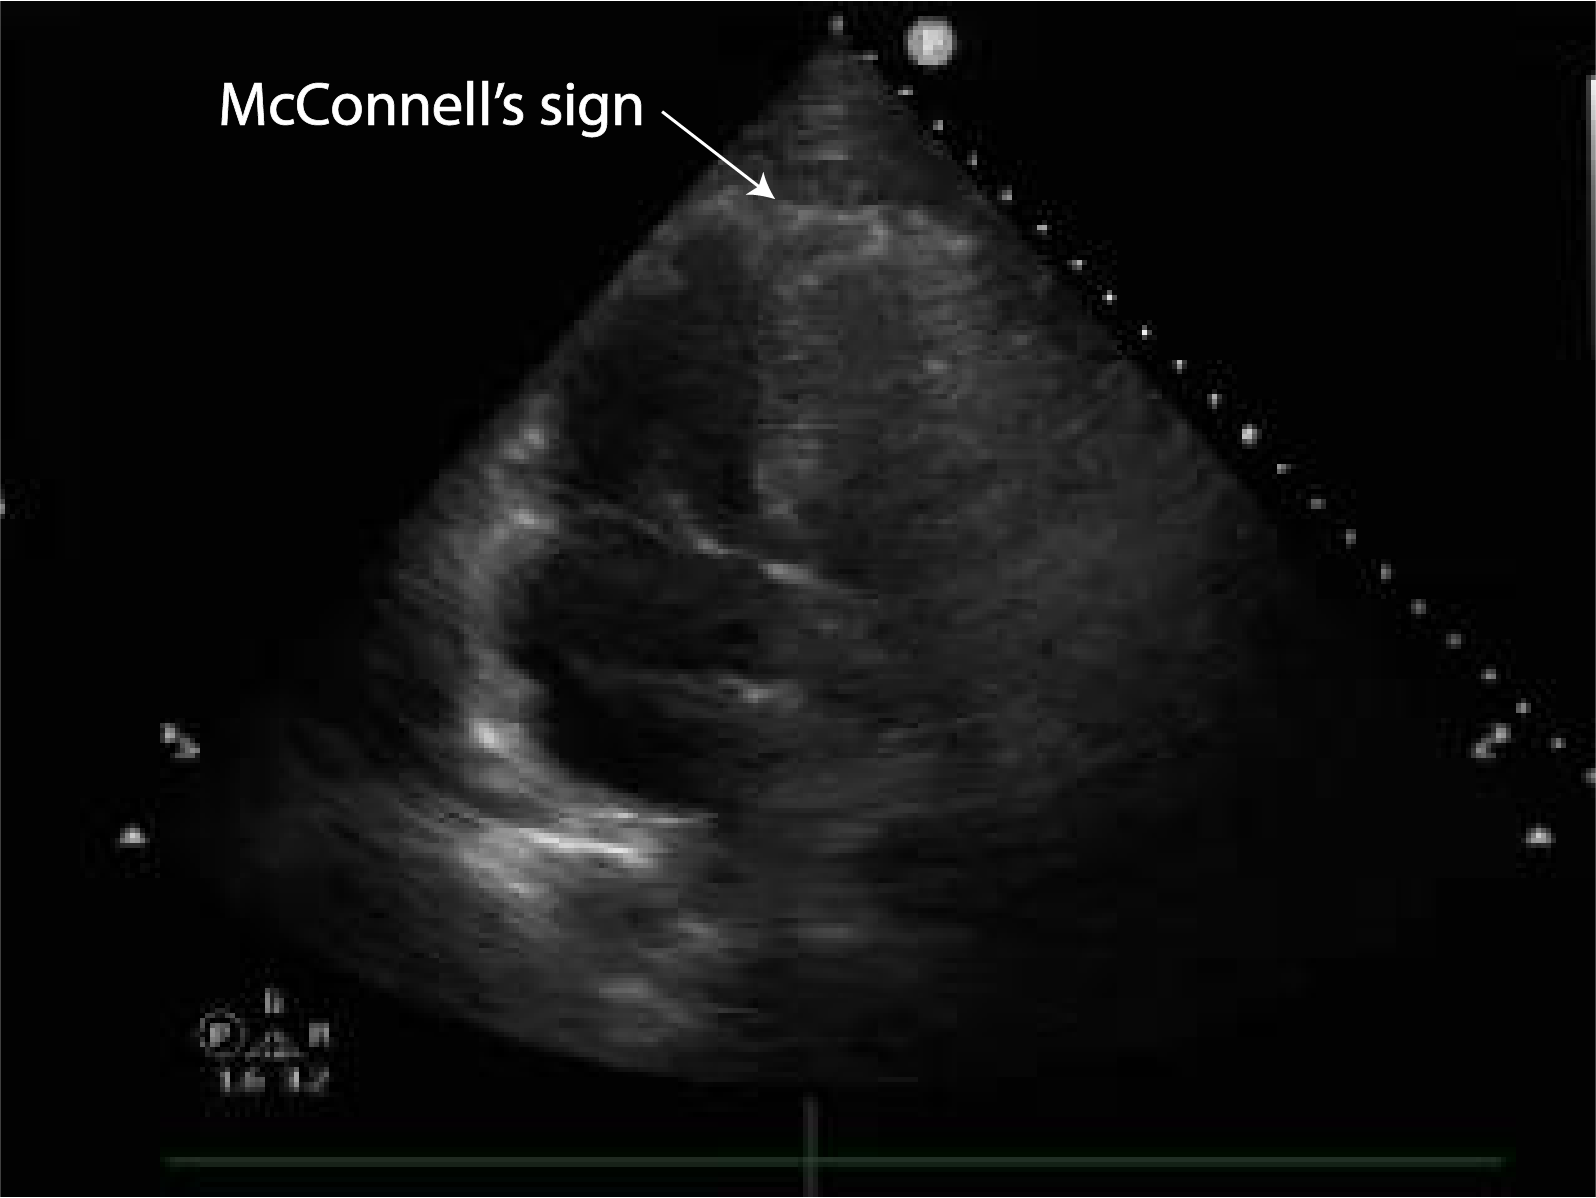

Discover how the McConnell sign echo serves as a critical diagnostic marker for acute pulmonary embolism. Learn how this specific echocardiographic finding—characterized by right ventricular free wall akinesia with apical sparing—aids clinicians in rapid assessment, heart strain evaluation, and differentiating cardiac conditions to ensure accurate patient diagnosis and improved clinical outcomes in emergency medicine.